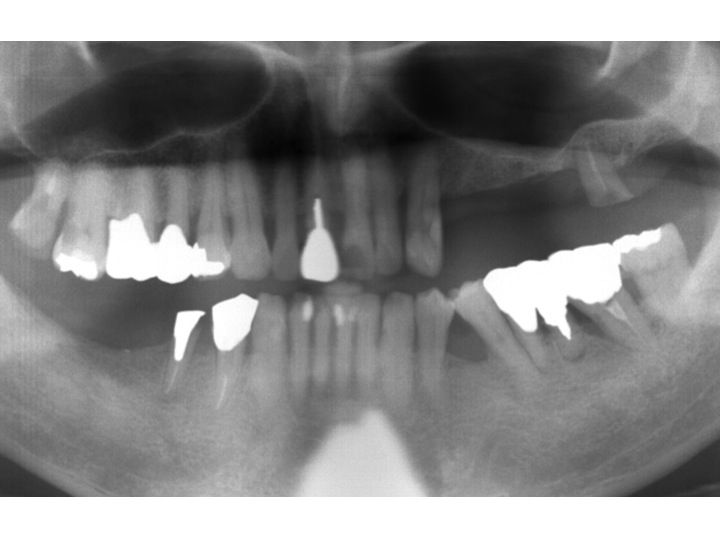

以下が初診時のレントゲンです。

歯自体はグラグラなので、

まず抜歯し、義歯を作製することになりました。

次のステップとして、インプラント治療の計画を立てます。